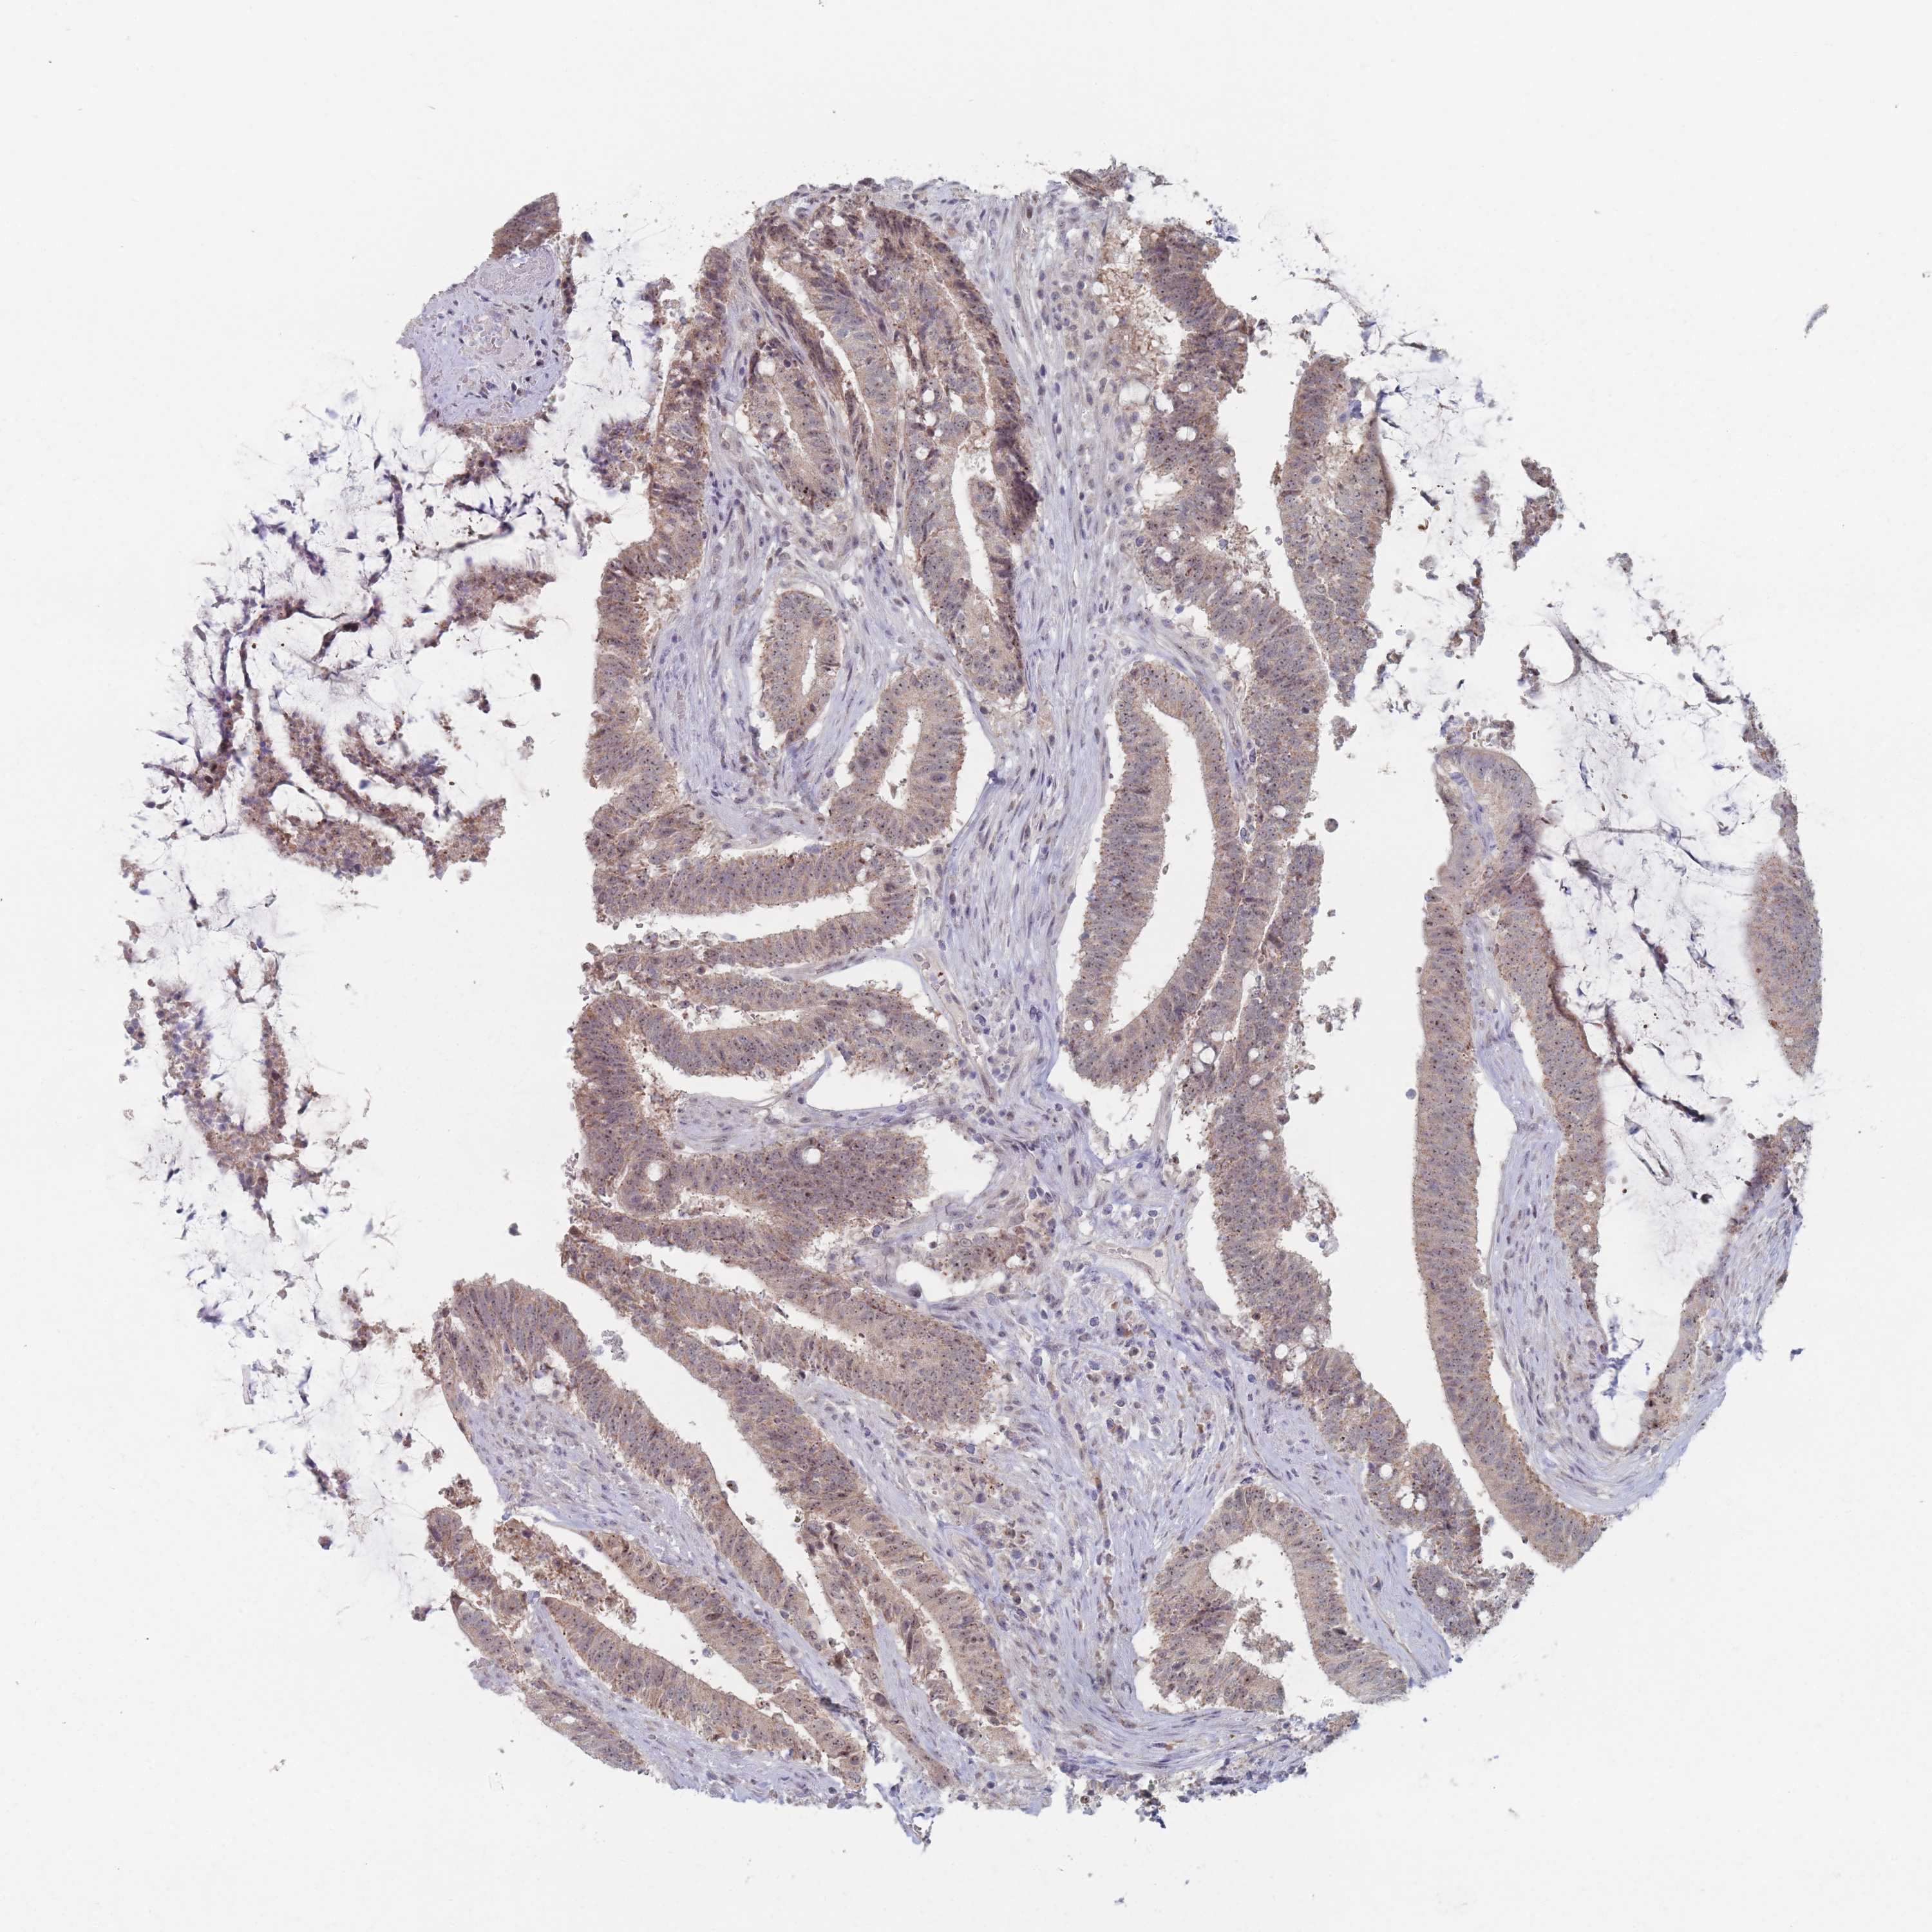

Colorectal cancer

Colon adenocarcinoma